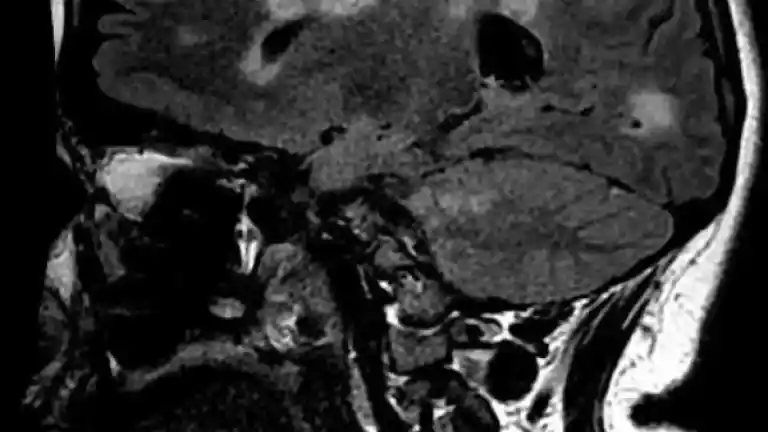

Imagen 1 de Otro estudio apunta a la relación entre el virus de la mononucleosis y la esclerosis múltiple